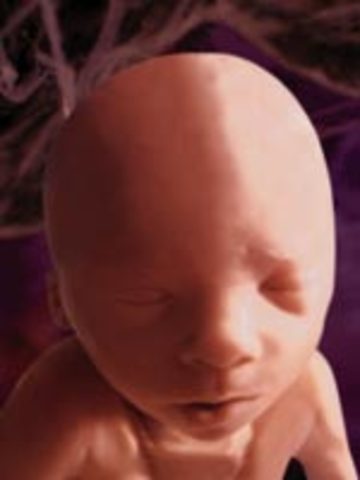

• week 12 Nails

week 12 Nails

the fetus finishes developing its facial profial and finishes developing its vocal chords. the fetus' brain is fuly formed and it feels pain, its pancreas will begin making insulin and the fetus will such on its fingers.

Fact: the fetus will cry silently occasionally in its mothers womb, the fetus has reached 2.5 inches and weighs 0.7 ounces